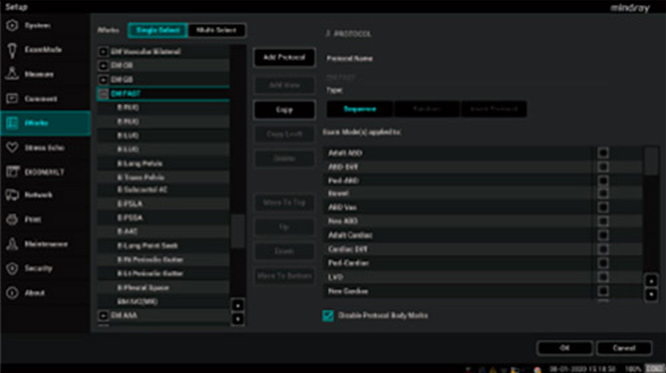

Aliviar la presiÃģn sobre el personal del Departamento de Emergencias, mejorar la velocidad y la precisiÃģn de la toma de decisiones clÃnicas, y salvar la vida de los pacientes. Dise?amos la ecografÃa de punto de atenciÃģn de la serie ME con el workflow de emergencia en mente. Se proporcionan configuraciones definidas por el usuario a fin de priorizar las sondas y los workflows de examen mÃĄs utilizados para cambiarlas con un solo clic, y se integra una variedad de protocolos rÃĄpidos de ecografÃa de cabecera, como FAST y EFATE, para permitir que los mÃĐdicos evalÚen de manera adecuada y rÃĄpida el estado del paciente en casos de emergencia.

Protocolos para exÃĄmenes de emergencia en la ecografÃa de punto de atenciÃģn de Mindray.

Aliviar la presiÃģn sobre el personal del Departamento de Emergencias, mejorar la velocidad y la precisiÃģn de la toma de decisiones clÃnicas, y salvar la vida de los pacientes. Dise?amos la ecografÃa de punto de atenciÃģn de la serie ME con el workflow de emergencia en mente. Se proporcionan configuraciones definidas por el usuario a fin de priorizar las sondas y los workflows de examen mÃĄs utilizados para cambiarlas con un solo clic, y se integra una variedad de protocolos rÃĄpidos de ecografÃa de cabecera, como FAST y EFATE, para permitir que los mÃĐdicos evalÚen de manera adecuada y rÃĄpida el estado del paciente en casos de emergencia.

Protocolos para exÃĄmenes de emergencia en la ecografÃa de punto de atenciÃģn de Mindray.